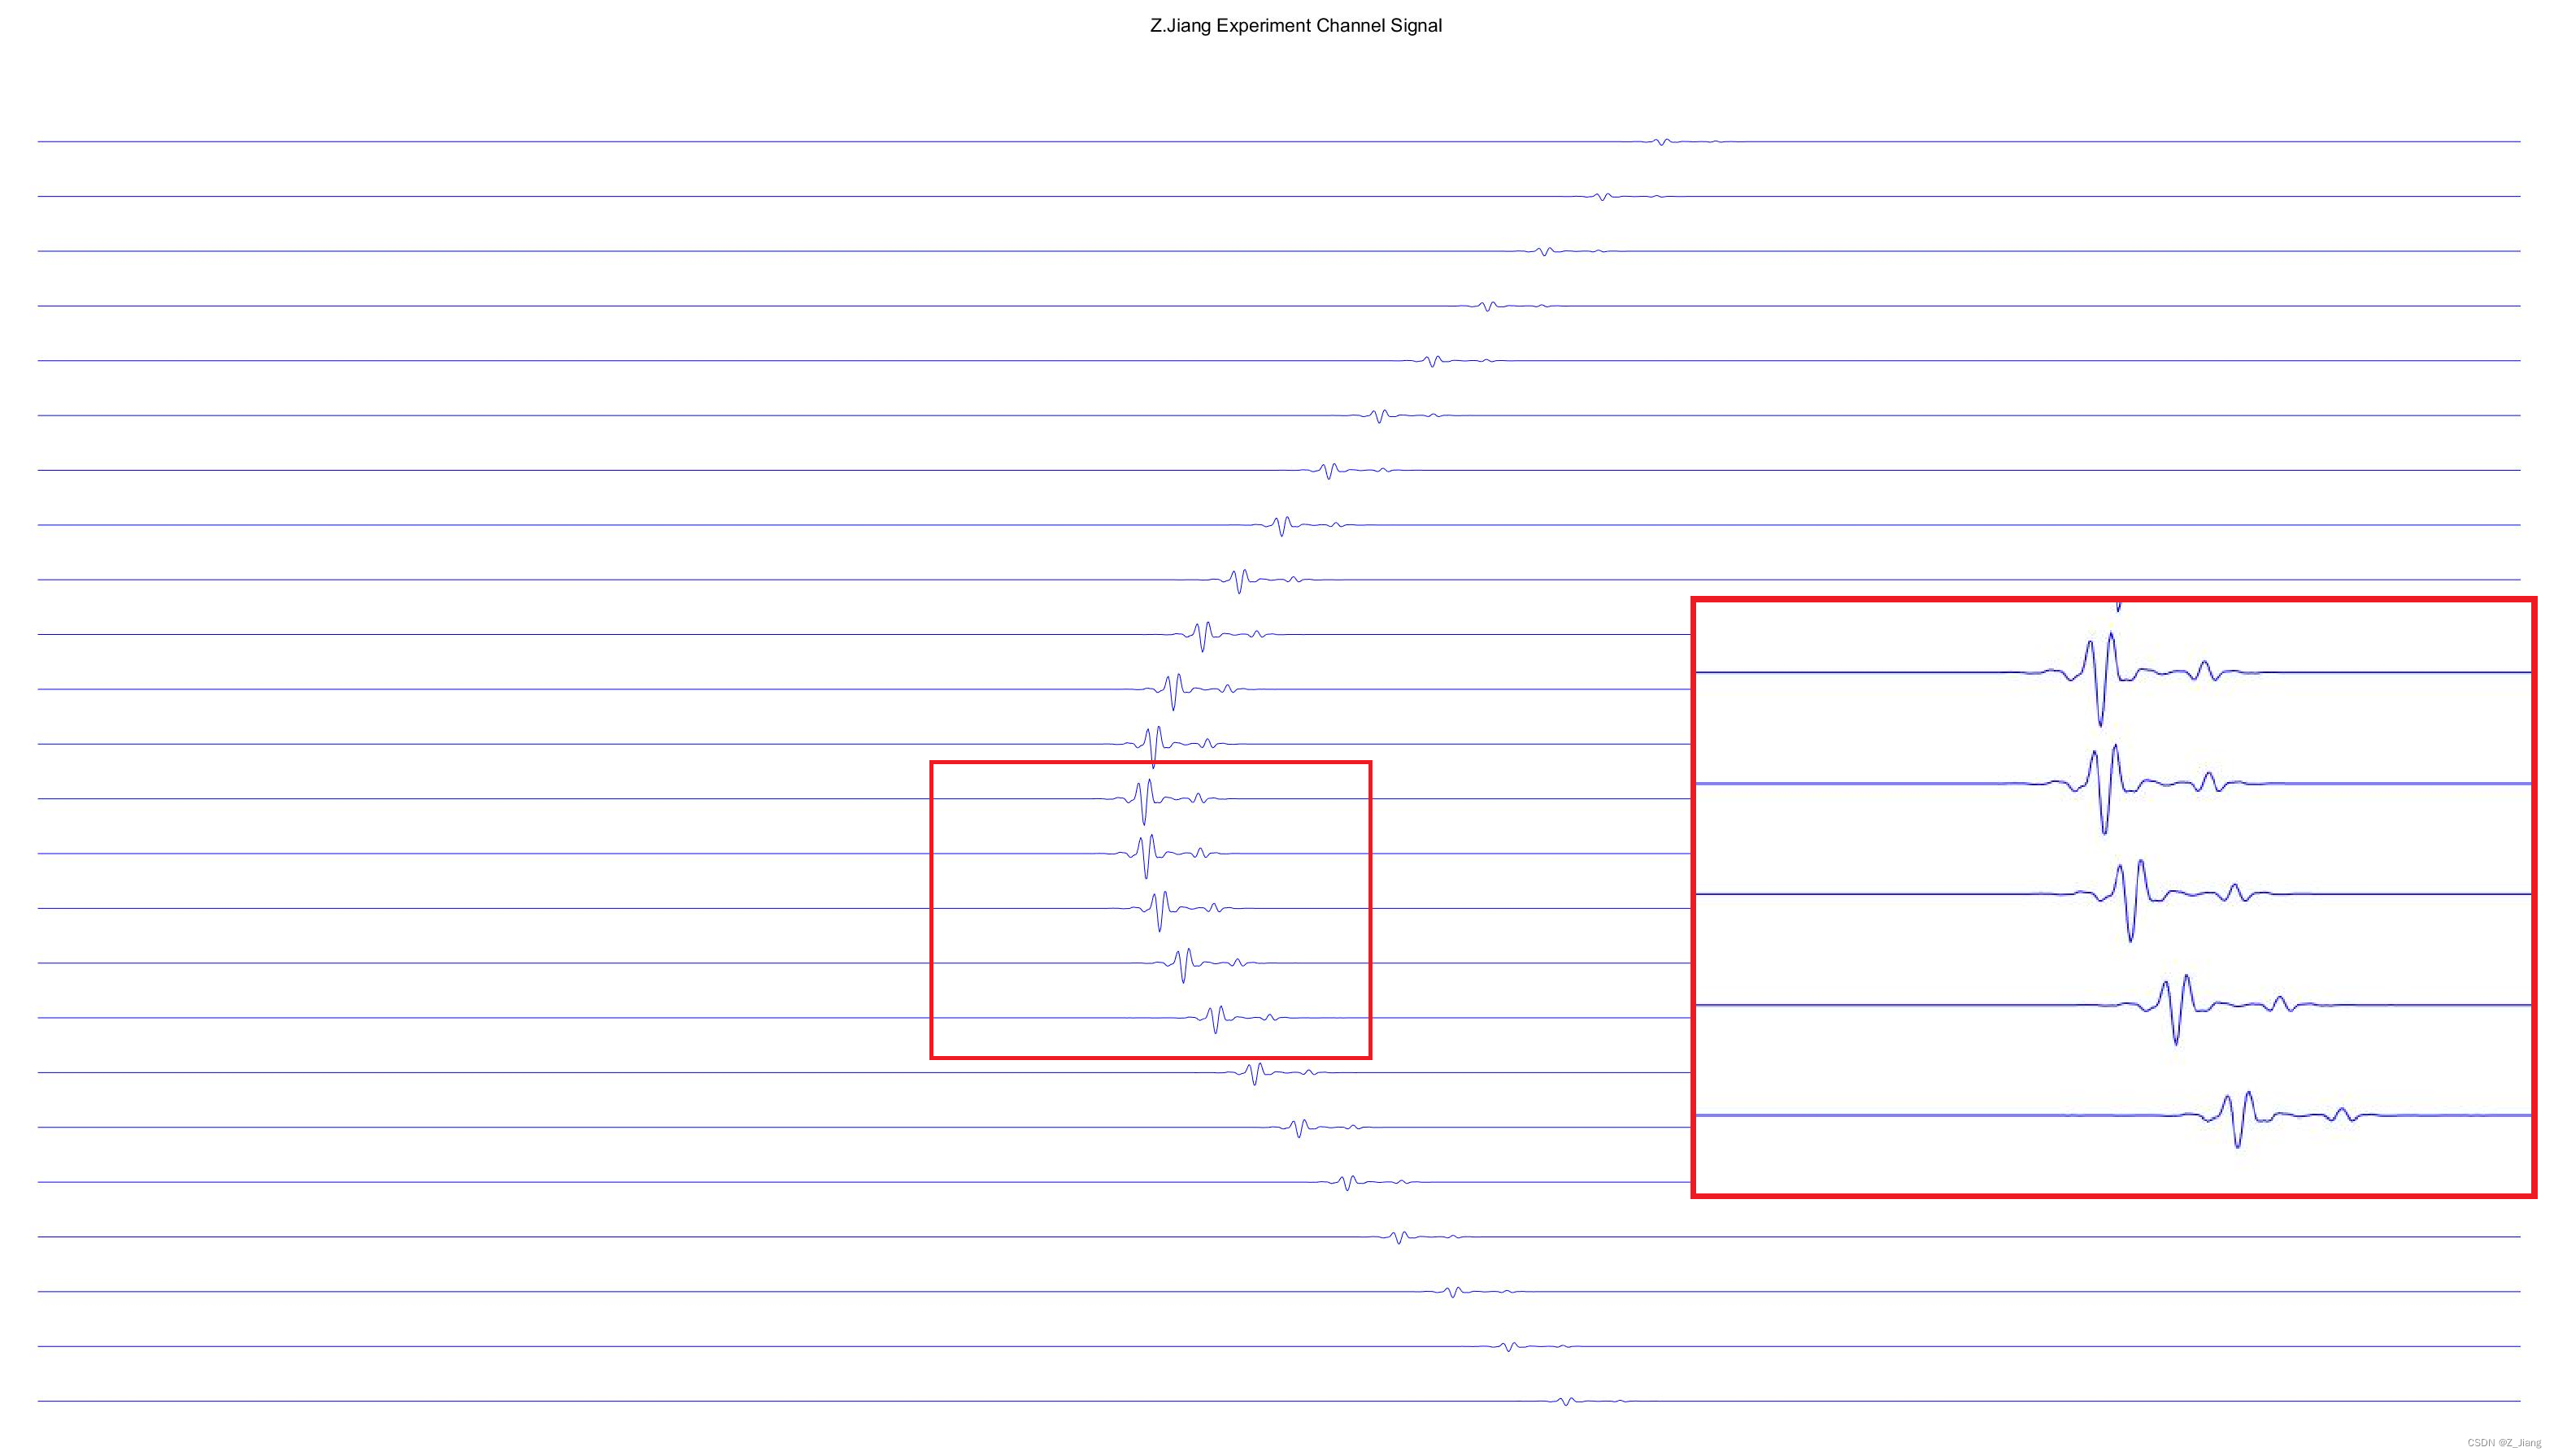

上面的交互过程的反射信号,被探头接收转换为电信号后,就是我们说的通道数据。下图是上组实验中接收到的信号;

怕大家看不清楚,红色框内,我拉大了显示; 每个通道的信号,基本长得和激励发射时的波形一样。实际上这是不对的,因为彩超系统不是线性系统,且声音在传播过程中也是非线性的,波形也会逐步发生畸变,所以我们的仿真不是太真,不过基本够用。你一认真,就输了。